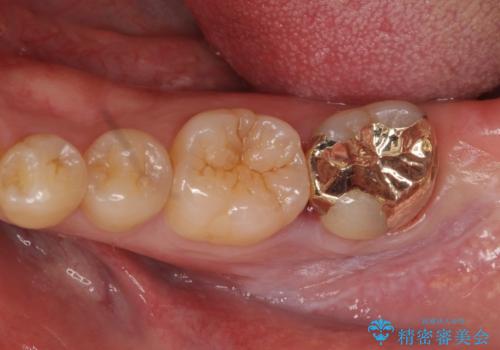

欠けた詰め物 セラミッククラウンでの修復

担当医 岡田康成